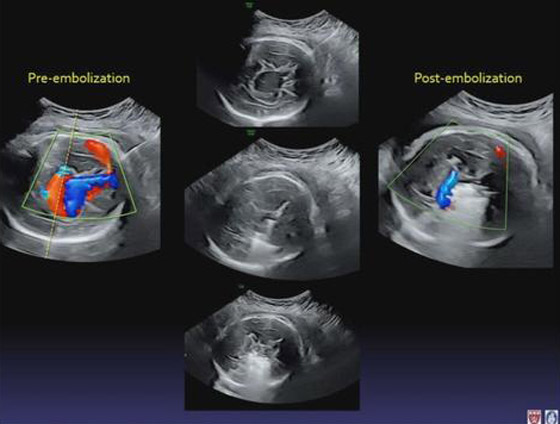

في حين أُجرِيَت العملية على جنينٍ عمره 34 أسبوعاً من الحمل؛ حيث أُدخِلَت إبرة في رحم والدته. واستُخدِمَت صور الموجات فوق الصوتية لتوجيهها عبر مؤخرة رأس الجنين. ثم استُخدِمَت الإبرة لوضع قسطرة في الوعاء الدموي المُوصِل غير الطبيعي، وإدخال لفافة معدنية خاصة لتقليل عرض الوعاء الدموي؛ وبالتالي إبطاء تدفق الدم. واستغرقت العملية أقل من ساعتين، وكانت الأم والجنين تحت التخدير. ووُلِدَت الطفلة قبل أوانها، بعد العملية بيومين.